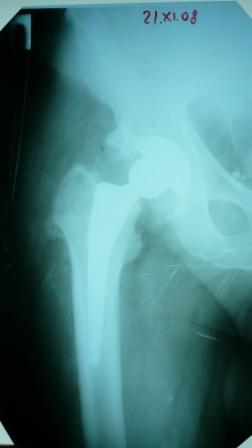

Больное выписан. Рекомендована ходьба без нагрузки 6 нед, рентгеноконтроль через 2 мес. Явка на консультацию На консультации через 7 недель-

Больной ходит с дозированной нагрузкой, умеренные боли по задней поверхности правого бедра.  Планируется ревизия. Удаление ножки. Установка такой же ножки Corail.

Приходилось ли кому встречаться с такой ситуацией?

Вопросы: вросла ли ножка? Какие могут возникнуть сложности с удалением ножки? Нужна ли будет дополнительная трепанация диафиза? И как? Правильный выбор ножка Corail для ревизии в такой ситуации?